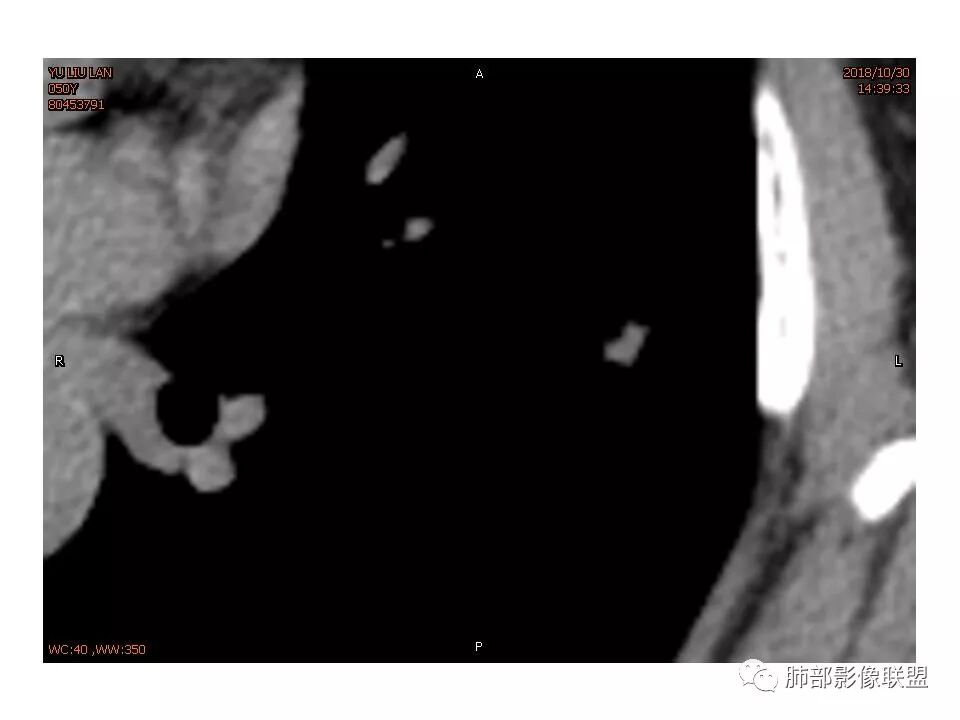

女性,50岁。U型凹陷、平直征

南边:支持炎性

这些层面不大放心

南边 :

我倾向于炎性结节,癌待排

如果病灶边缘模糊加桃尖或u形征,当病人除外咳血症状,对于炎症诊断支持较大?

因为南大说过实性病变有收缩力往往是慢性炎症。而腺癌毛玻璃才会牵拉叶间裂

有一些地方膨隆,肯定不放心,但是大部分还是平直收缩,要我读片我也炎症放前面,肺癌待排。但是现实生活我会建议切除

轴位像炎性,冠状、矢状位像恶性,真遇到了,纠结

1.胸膜下略不规则实性密度结节影,孤立,缺乏典型深分叶,可见淡薄边界模糊磨玻璃晕,可见相对细长软毛刺。

2.如南边老师分析,病灶缺乏边缘膨隆优势,甚至部分平直内收。

3.病灶收缩力不强,整体强化程度不显著。

4.综上,病灶更符合炎性,如隐球菌感染等,而不大符合肺腺癌。具体到机化性肺炎略有些出乎预料。